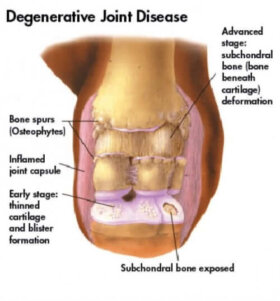

골관절염이라고도 부르는 퇴행성 관절염은 히알린 연골 및 준연골 뼈에 영향을 미치는 질환이다. 퇴행성 관절염의 발병으로 인해 통증, 염증이 생기고 평소처럼…